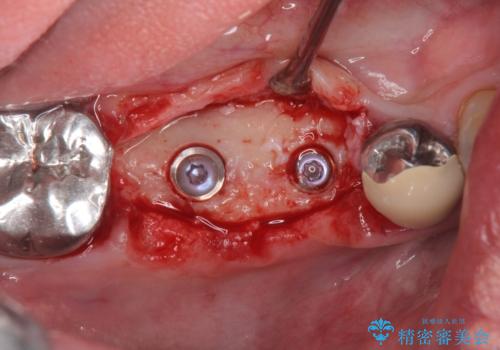

支台を増やし、残った歯の負担を減らし守るために欠損部位にインプラントを埋入し咬合力の負担に対応できる環境を整えます。

- 105.4万円(仮歯×4・ストローマンインプラント×2・チタンカスタムアバットメント×2・ジルコニアクラウン×4)費用は治療当時の料金となります

インプラント治療は、ブリッジや入れ歯と異なり人口の歯根となるインプラントを顎骨内に埋入することで咬合力に耐える支台を増やせるというメリットがあります。

残った歯の負担を減らすことでより長期的な予後を期待することができます。